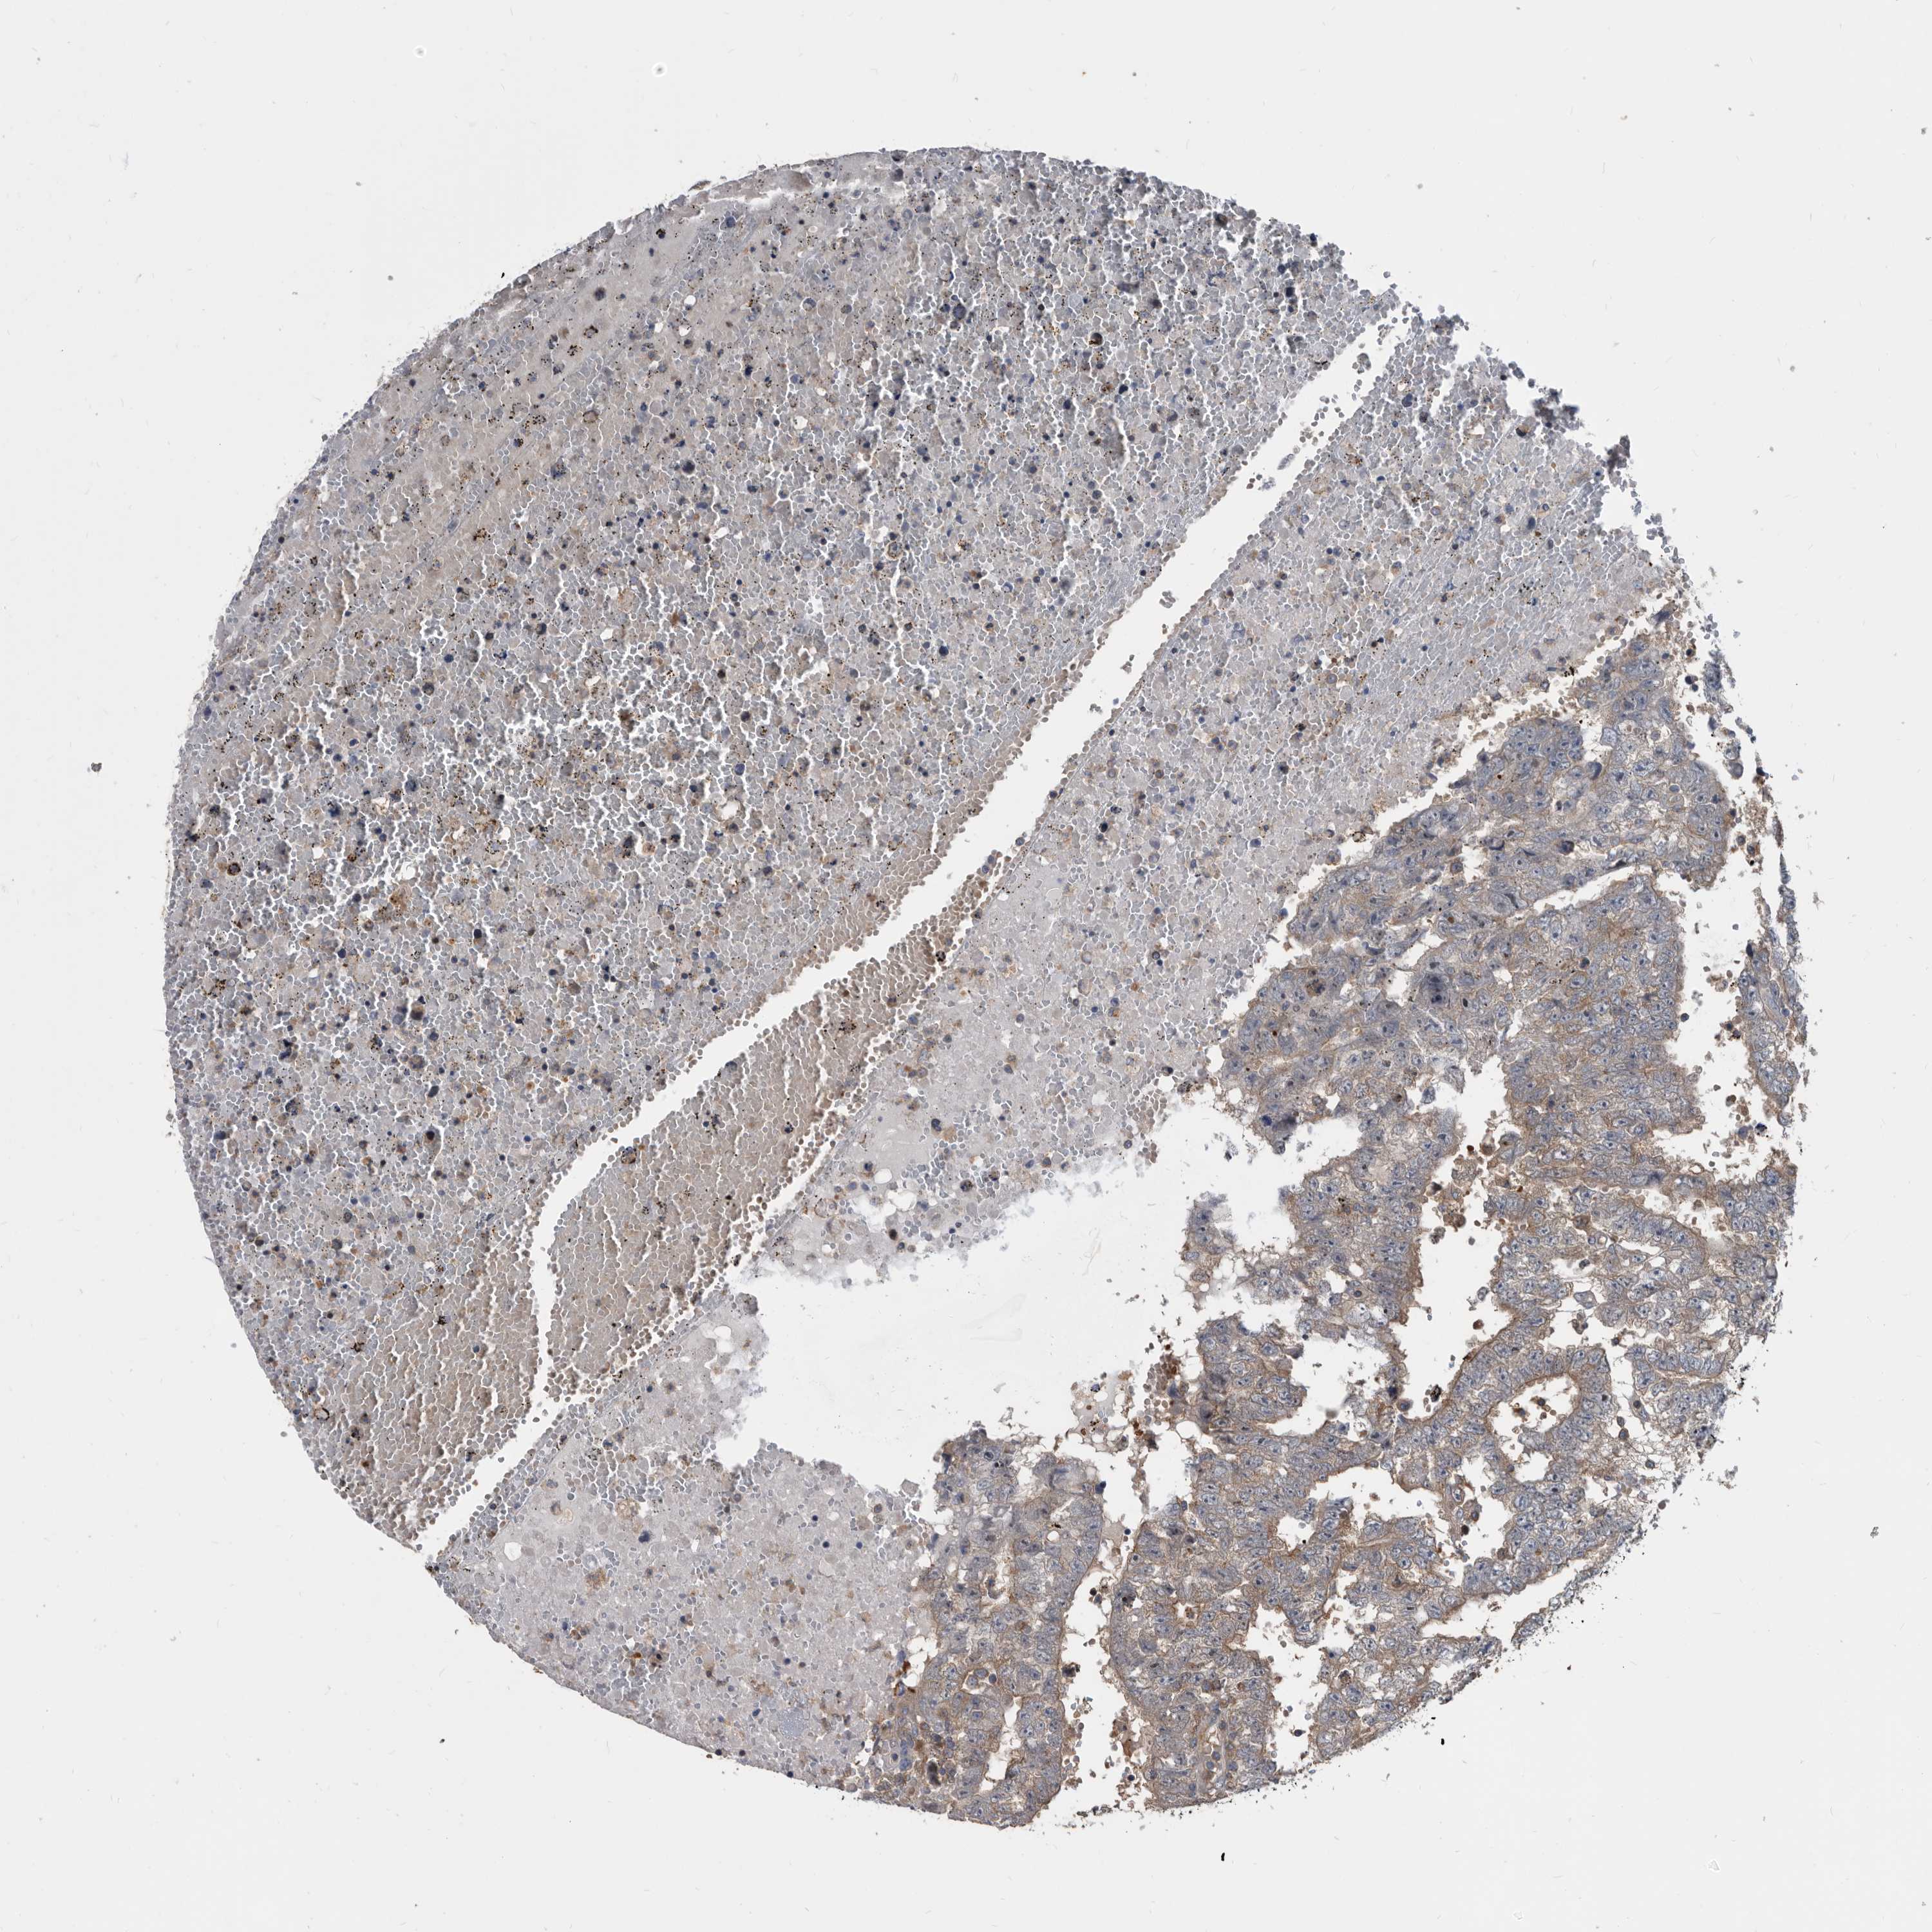

TESTIS CANCER - Protein expressioni

A mouse-over function shows sample information and annotation data. Click on an image to view it in a full screen mode. Samples can be filtered based on level of antibody staining by selecting one or several of the following categories: high, medium, low and not detected. The assay and annotation is described here.

Note that samples used for immunohistochemistry by the Human Protein Atlas do not correspond to samples in the TCGA dataset.

Antibody stainingi

Antibody staining in the annotated cell types in the current human tissue is reported as not detected, low, medium, or high, based on conventional immunohistochemistry profiling in selected tissues. This score is based on the combination of the staining intensity and fraction of stained cells.

Each image is clickable and will lead to virtual microscopy that enables deeper exploration of all samples and also displays staining intensity scores, fraction scores and subcellular localization as well as patient and tissue information for each sample.

Antibody HPA029700

Antibody HPA029701

Antibody HPA029702

Antibody HPA029703

Carcinoma, Embryonal, NOS

Seminoma, NOS